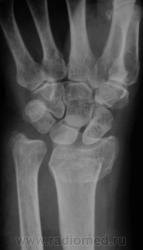

Случай 2.  Пациент направлен врачом хирургом на рентгенографию лучезапястного сустава.

А вот по-поводу второго случая: перелом луча в "типичном" месте, только вот смущает ладьевидная кость - какая-то она патологическая, имеется участок разряжения костной ткани в проекции головки кости или я ошибаюсь?